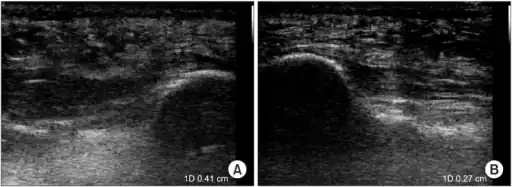

a)Ultrasonographic finding of plantar fasciitis b)normal sonographic finding

The plantar fascia has three fascicles-the central fascicle being the thickest at 4 mm, the lateral fascicle at 2 mm, and the medial less than a millimeter thick.[18] In theory, plantar fasciitis becomes more likely as the plantar fascia's thickness at the calcaneal insertion increases. A thickness of more than 4.5 mm ultrasound and 4 mm on MRI are useful for diagnosis.[19] Other imaging findings, such as thickening of the plantar aponeurosis, are nonspecific and have limited usefulness in diagnosing plantar fasciitis.[13]